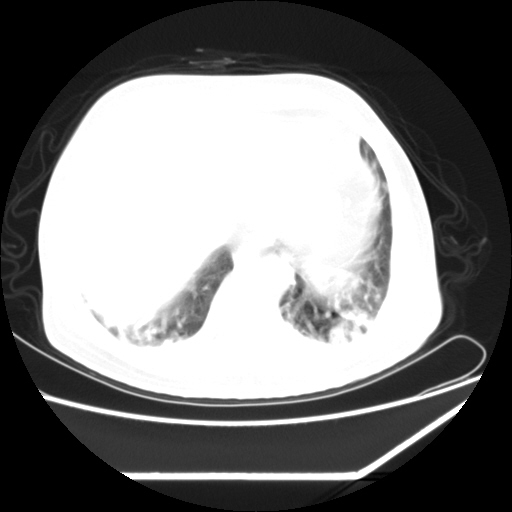

男,57,畏寒,发热

两侧多发肺脓肿,两侧胸膜增厚,抗炎治疗后复查

畏寒发热,首先考虑血源性肺脓肿,结合临床,抗炎后复查排除转移瘤等。

首先考虑血源性肺脓肿

血源性肺脓肿

血源性肺脓肿,除外转移瘤